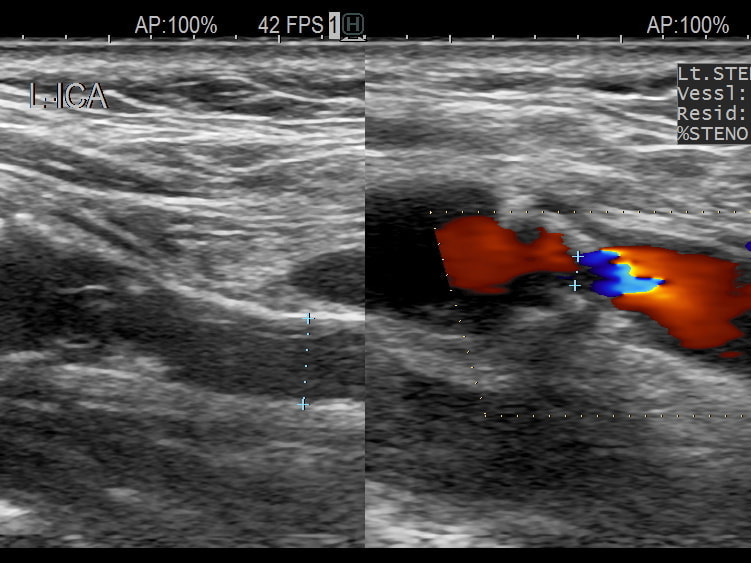

• 頚動脈超音波検査:頚動脈プラークの大きさや性状から、脳梗塞の危険性などがわかります。